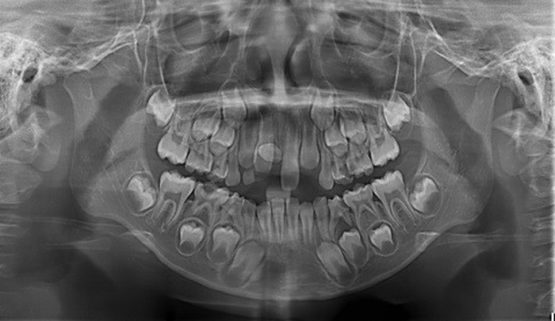

- Kiểm tra, phát hiện các răng khôn có bị mọc lệch, mọc ngầm, mọc chen chúc với răng số 7, răng có xuyên vào nướu không.

- Quan sát được tiến trình mọc răng của trẻ em.

Cùng 1 liều bức xạ khi chụp X-quang, tùy và giai đoạn tuổi thai mà mức độ ảnh hưởng của tia X gây ra với thai nhi sẽ khác nhau:

– Chụp X-quang khi mang thai 1 tuần: Chưa có nghiên cứu rõ ràng về ảnh hưởng của tia X đến giai đoạn này.

– Chụp X-quang khi mang thai 2 tuần- 7 tuần: Có nguy cơ ảnh hưởng đến thai nếu liều bức xạ cao.

– Chụp X-quang khi mang thai 8- 40 tuần: Có nguy cơ ảnh hưởng đến thai nếu liều bức xạ cao.

Ngoài tuổi thai, mức độ ảnh hưởng của tia X đến thai nhi cũng phụ thuộc vào vị trí cơ quan được chụp. Cụ thể hơn: